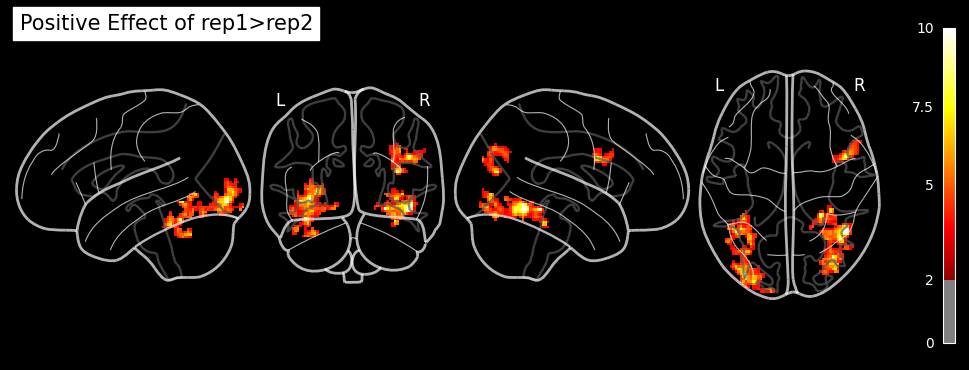

rep1 = ('Positive effect of Rep', 'T', condition_names, [1, -1, 1, -1, 1, -1])